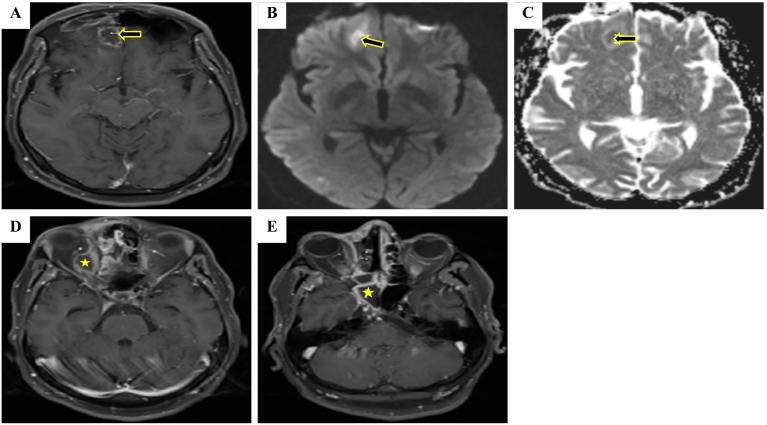

CASE PRESENTATION

we report two cases of brain abscess as a complication of nasopharyngeal COVID-19 testing. The first case was of a 47-year-old male diabetic patient with a positive medical history for immune thrombocytopenic purpura (ITP) who developed a frontal brain abscess one week after the swabbing procedure and was treated with systemic antibiotics followed by a successful functional endoscopic sinus surgery. The second case involved a hypertensive female patient in her 40s who also developed a frontal brain abscess on the same side as painful nasal COVID-19 testing. Systemic antibiotics were used to treat the patient.

我们报告两例因新冠病毒鼻咽检测引发脑脓肿并发症的病例。首例为一名47岁男性糖尿病患者,有免疫性血小板减少性紫癜(ITP)病史,在拭子采样操作一周后发生额叶脑脓肿,接受全身抗生素治疗,随后成功进行了功能性鼻内镜鼻窦手术。第二例涉及一名40多岁的高血压女性患者,在进行痛苦的新冠病毒鼻咽检测后,同侧也发生了额叶脑脓肿。对该患者使用了全身抗生素进行治疗。